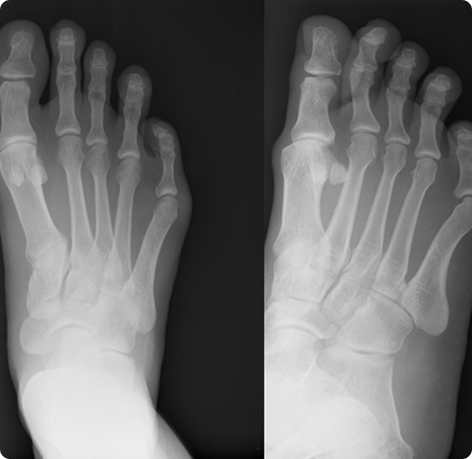

Pre op AP view hammer toes 2-5

Post op oblique and AP views hammer toes 2-5

Pre op oblique view - hammer toes #2 and 3

Post op AP view hammer toes 2-5